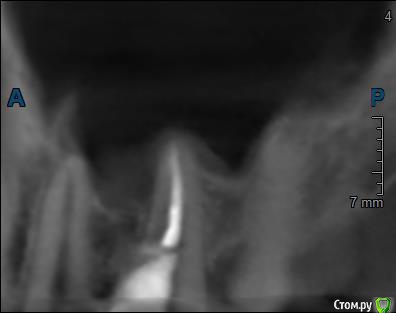

Здравствуйте! Верхний правый шестой зуб пломбировали 3 месяца назад. Примерно месяц назад он начал ныть, после насморка, сначала периодами, а теперь почти постоянно. При постукивание (ощущается не совсем так, как другие зубы) и пальпации десны он не болит. 2,5 месяца назад удаляли кисту из гайморовой пазухи. Может ли быть это какое-то воспаление и есть ли вероятность устранить его какими-нибудь антибиотиками, если да, то как, или может удалить зуб? Если есть воспаление, то какие могут быть последствия если не удалить зуб?

(Снимки с КТ, первые 8(Image) - сделаны сейчас,по 4 в разных проекциях, вторые 8(Before) - сделаны 5 месяцев назад до удаление кисты и повторного пломбирование зуба( до повторного пломбирование он реагировал на горячее, был запломбирован 3 года))

переличили зуб адекватно, во всяком случае по снимкам